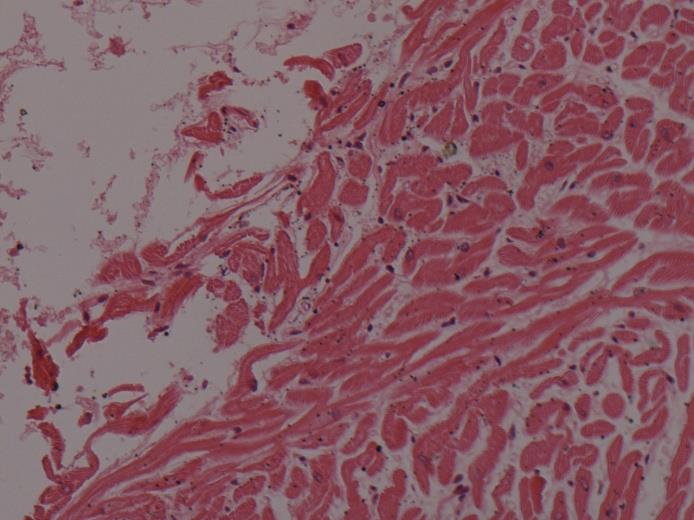

组织病理学检查:心外膜破裂口处脂肪组织内出血(图5),仅破裂口周围心肌嗜酸性变,部分心肌收缩带坏死(图6);其余心肌未见坏死、炎症,未见破口周边的心肌组织有大范围梗死灶。其余器官除淤血、水肿外未见明显异常。

图6破裂口周围部分心肌收缩带坏死(HE×200)